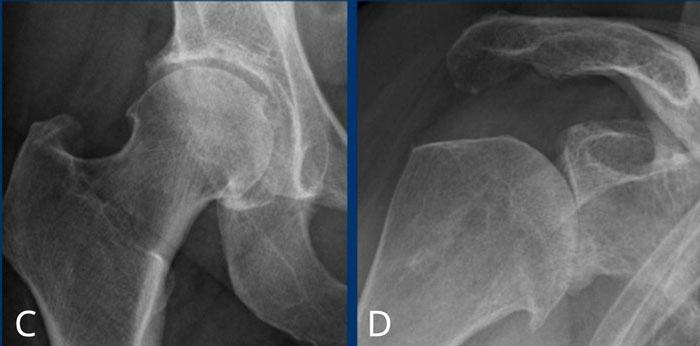

C

Hẹp nhẹ khe khớp háng phía trên bên phải kèm hình thành gai xương và xơ cứng xương dưới sụn (phân loại Kellgren-Lawrence độ 3).

D

Hẹp nặng khe khớp ổ chảo-cánh tay kèm hình thành gai xương và xơ cứng xương dưới sụn (phân loại Kellgren-Lawrence độ 4).

Thoái hóa khớp háng

Hẹp nặng khe khớp háng không đồng đều kèm hình thành gai xương, xơ cứng xương dưới sụn và nang xương kích thước lớn.

Ở giai đoạn muộn, có thể xuất hiện biến dạng khớp với hiện tượng mở rộng và biến dạng chỏm xương đùi.

Thoái hóa khớp gối

Hẹp khe khớp đùi-chày khoang trong mức độ vừa đến nặng, không đối xứng, kèm hình thành gai xương và xơ cứng xương dưới sụn (phân loại Kellgren-Lawrence độ 3-4).